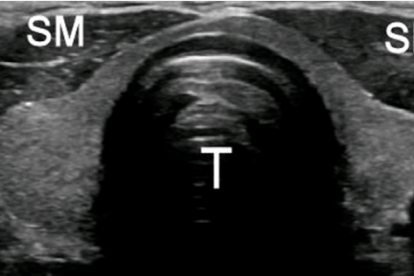

山东第一医科大学附属省立医院内分泌科在甲状腺疾病诊疗领域具有较高声誉。医院引进了的甲状腺超声设备和实验室检测技术,能够为桥本氏病患者提准的诊断和治疗。